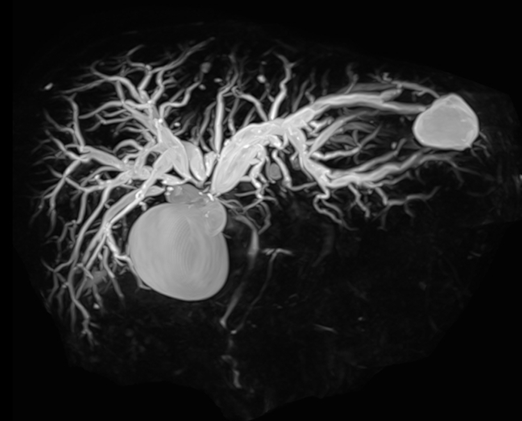

肝門部領域胆管癌による胆道狭窄に対して胆道ドレナージを行った症例

肝門部領域胆管癌によって閉塞性黄疸を発症し、複数のステントを留置した症例を示します。

本症例では化学療法中に黄疸が出現しました。MRCP検査では、胆管の左枝、前区域枝、後区域枝のそれぞれに狭窄を認めました。

ERCPを行ったところ、同様にこれらの胆管に狭窄を認めたため、それぞれの胆管に対して胆汁の流れを確保する必要がありました。そのため、3本のプラスチックステントを留置しました。

ステント留置後、黄疸は速やかに改善し、その後化学療法を再開することができました。

また、複数本のステントが必要な状況であっても、症例ごとの病状や胆管の走行、狭窄の形態などを考慮し、金属ステントを留置することもあります。当科では、一人ひとりの状態に合わせて、最適な胆道ドレナージを行うよう心がけています。